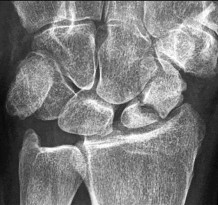

- الأشعة السينية (X-rays): هي الخطوة الأولى في تقييم الكسور، الخلوع، وتغيرات التهاب المفاصل. تساعد في تحديد مدى تدهور العظام والمسافات المفصلية. على سبيل المثال، تُظهر صور الأشعة السينية كسور السلاميات

أو كسور قاعدة العظم المشطي الخامس

، بالإضافة إلى علامات مثل "الدمعة الشعاعية" (Radiographic Teardrop) في الرسغ التي تمثل الزاوية الزندية الراحية الحرجة للكعبرة البعيدة

. - الأشعة المقطعية (CT Scan): توفر صوراً تفصيلية ثلاثية الأبعاد للعظام، وهي مفيدة جداً لتقييم الكسور المعقدة، مثل كسور العظم الخطافي (Hamate Hook Fracture) التي قد لا تظهر في الأشعة السينية العادية